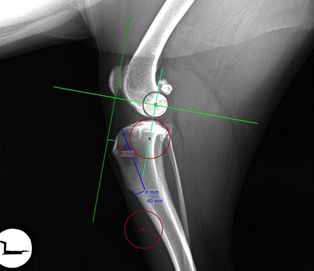

De röntgenfoto van de knie bepaalt hoeveel millimeter de kniepees naar voren moet worden verplaatst en welke maat kooi nodig is om de krachten op de voorste kruisband te neutraliseren. Ook wordt de dikte van de schors van het scheenbeen gemeten om zo de exacte plaats van de zaagsnede te bepalen.